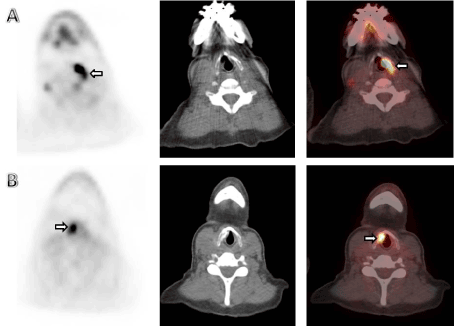

We present a 58 year old female with stage IV breast cancer, status bilateral mastectomies who underwent FDG PET/CT for follow up. The PET scan showed increased uptake in the left vocal cord (SUV max 3.9), consistent with right vocal cord paralysis presumably from a hypermetabolic right paratracheal node involving the recurrent laryngeal nerve (Figure 1A). Post-treatment axial PET, CT and fused PET/CT images showed focal intense FDG uptake in the right vocal cord at the CAHA injection site(SUV 9.2) (Figure 1B). Baseline FDG PET/CT scan showed a hypermetabolic right paratracheal adenopathy, the possible culprit for recurrent laryngeal nerve palsy.

Figure 1. (A) The PET scan showing increased uptake in the left vocal cord (SUV max 3.9), consistent with right vocal cord paralysis.

(B) Post-treatment  axial PET, CT and fused PET/CT images showing focal intense FDG uptake in the right vocal cord at the CAHA injection site(SUV 9.2).

Figure 1. (A) The PET scan showing increased uptake in the left vocal cord (SUV max 3.9), consistent with right vocal cgord paralysis.